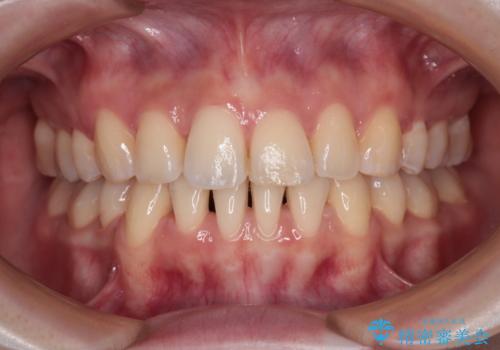

1年くらいの予定でしたが、わずか8ヶ月強で終えることができました。

ご希望の通り、安価に速やかに歯並びを改善することができ、患者様には大変満足していただきました。